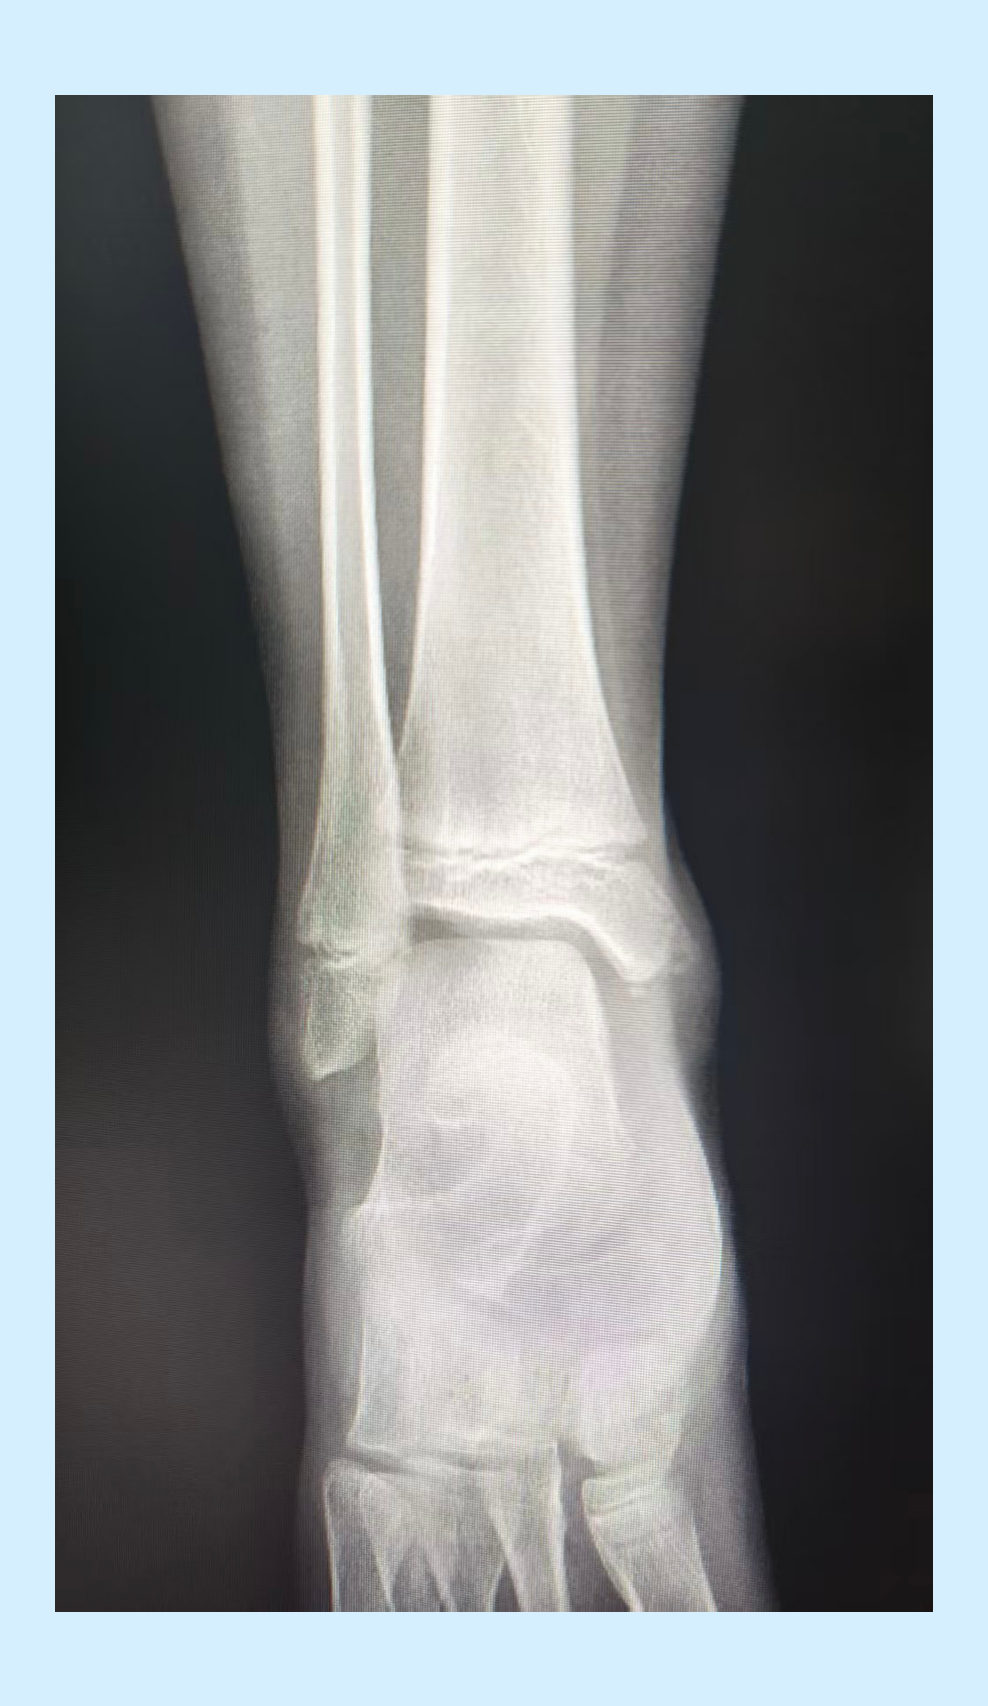

内踝骨折

内脚踝骨折